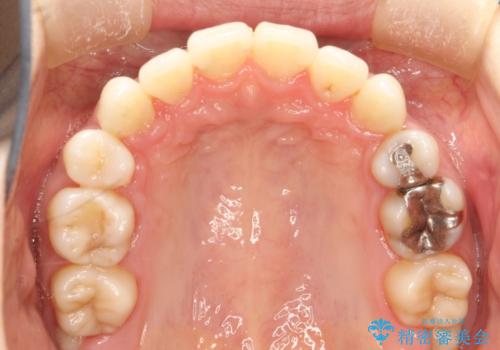

裏側のワイヤー矯正 抜歯して前歯をしっかり後ろに下げる

上顎の、前から4番目の歯を左右1本ずつ抜歯して前歯を後方に下げる計画としました。

目立たずに矯正をご希望でしたので、裏側矯正で治療を行いました。

上下裏側矯正であったため、舌に傷や口内炎ができるなどつらい経験もされましたが、目立たずに治療できたことに喜んでいただけました。